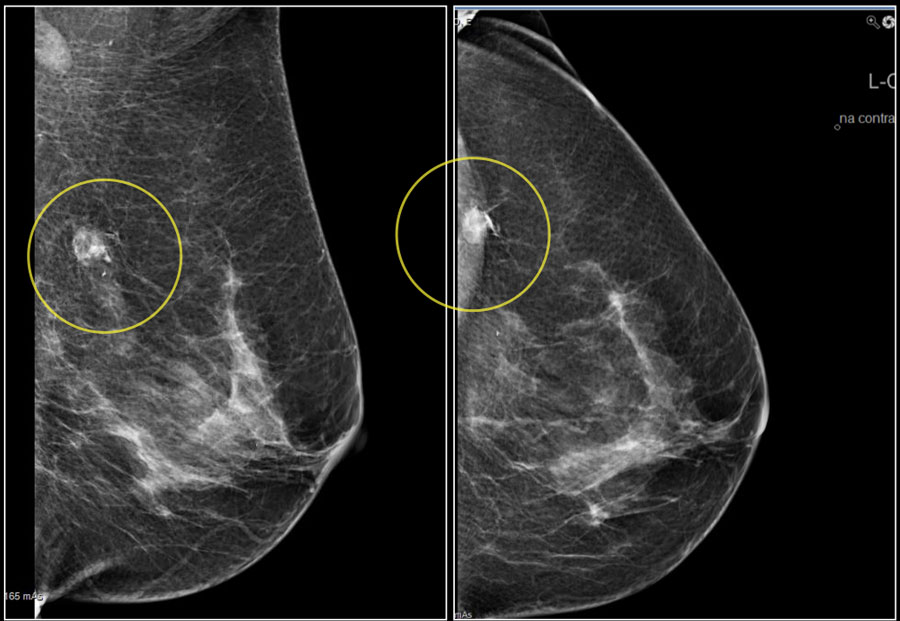

Ung thư vú

Khi bắt đầu bước sang tuổi 30, phụ nữ nhất định phải tập thói quen tự kiểm tra ngực hàng tháng. Cách đơn giản để phát hiện những bất thường là đứng trước gương tự sờ ngực và nằm ngửa sờ nắn ngực xem có những u cục lạ không. Nếu xuất hiện những cơn đau ngực bất thường, cần phải đi khám sớm để bác sĩ chẩn đoán kịp thời.

Nếu trong gia đình có chị em từng bị ung thư vú thì bạn nên cẩn thận đi xét nghiệm sớm. Phụ nữ sinh con muộn sau tuổi 30, người nghiện thuốc lá, uống rượu và bia cũng sẽ có nguy cơ mắc ung thư vú cao hơn.

Phụ nữ từ 40 tuổi trở lên là đối tượng dễ bị mắc bệnh ung thư vú cao gấp 3 lần so với những độ tuổi khác. Vì thế, phụ nữ cần chọn cho mình chế độ ăn uống, ngủ nghỉ, tập thể dục hợp lý và và nhất là phải thường xuyên khám ngực định kì.